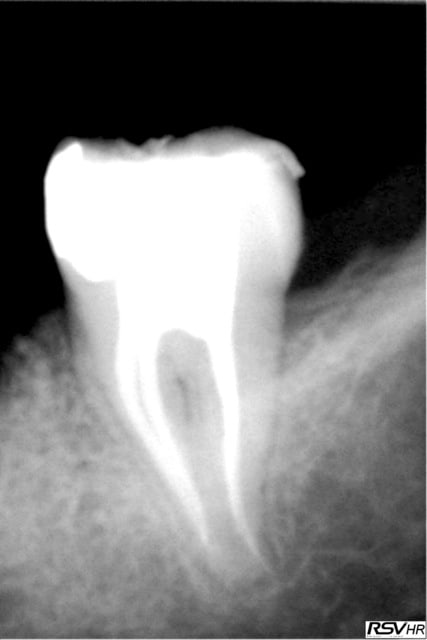

2 retraitements endo sur 45 46.

2 m85na9 - Eugenol

3 j2ewih - Eugenol

4 mbyxz8 - Eugenol

1 ojgvk3 - Eugenol